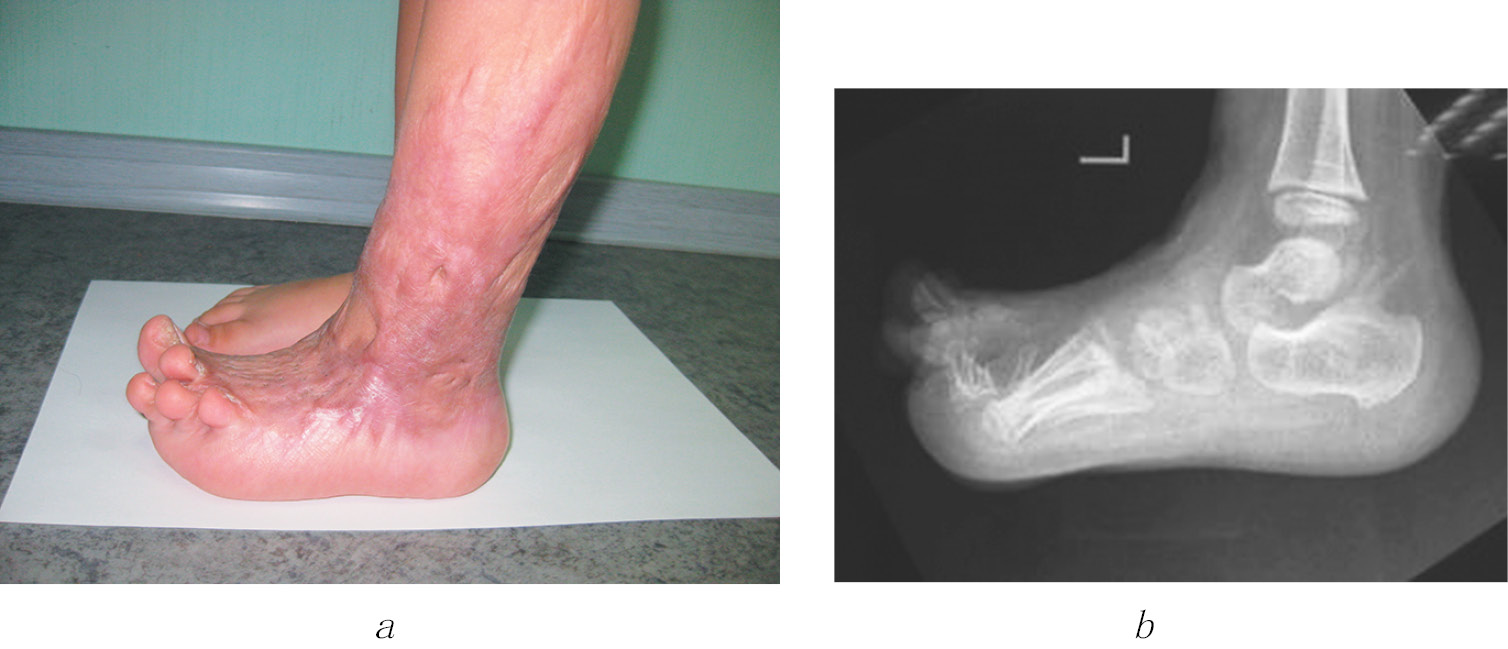

Flexion contractures in the metatarsophalangeal joints, which are generally associated with a lower frequency of burns on the plantar surface of the feet, were less commonly observed in this study. The transplantation of a sieve autograft on to the foot’s supporting surface always led to scar tissue hypertrophy and progressive trophic disorders (Fig. 5).

Fig. 5. Image of a 2-year-old diagnosed with flexion scar contractures in the metatarsophalangeal joint of the toe I 9 months after the restoration of the skin using sieve skin autografts. a, b — flexion contractures in the metatarsophalangeal joint of the toe I, retraction and hypertrophy of the established sieve skin autograft (clinical presentation); c, d — dislocations in the interphalangeal joints of the toe I (X-ray pattern)